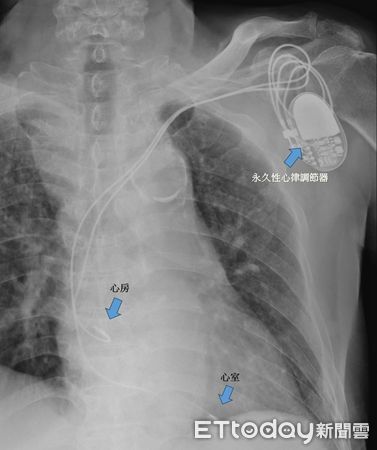

▲王伯伯植入心律調節器。(圖/記者許宥孺翻攝)

李冠華指出,對於二度II型及三度房室傳導阻滯患者,若排除其他因素仍心跳過緩無改善,則須考慮放置永久性心律調節器。該手術局部麻醉即可,將電極導線分別放入右心房及右心室後,心律調節器本體埋入上胸部皮下即可,手術安全性高,多數患者術後症狀顯著改善。